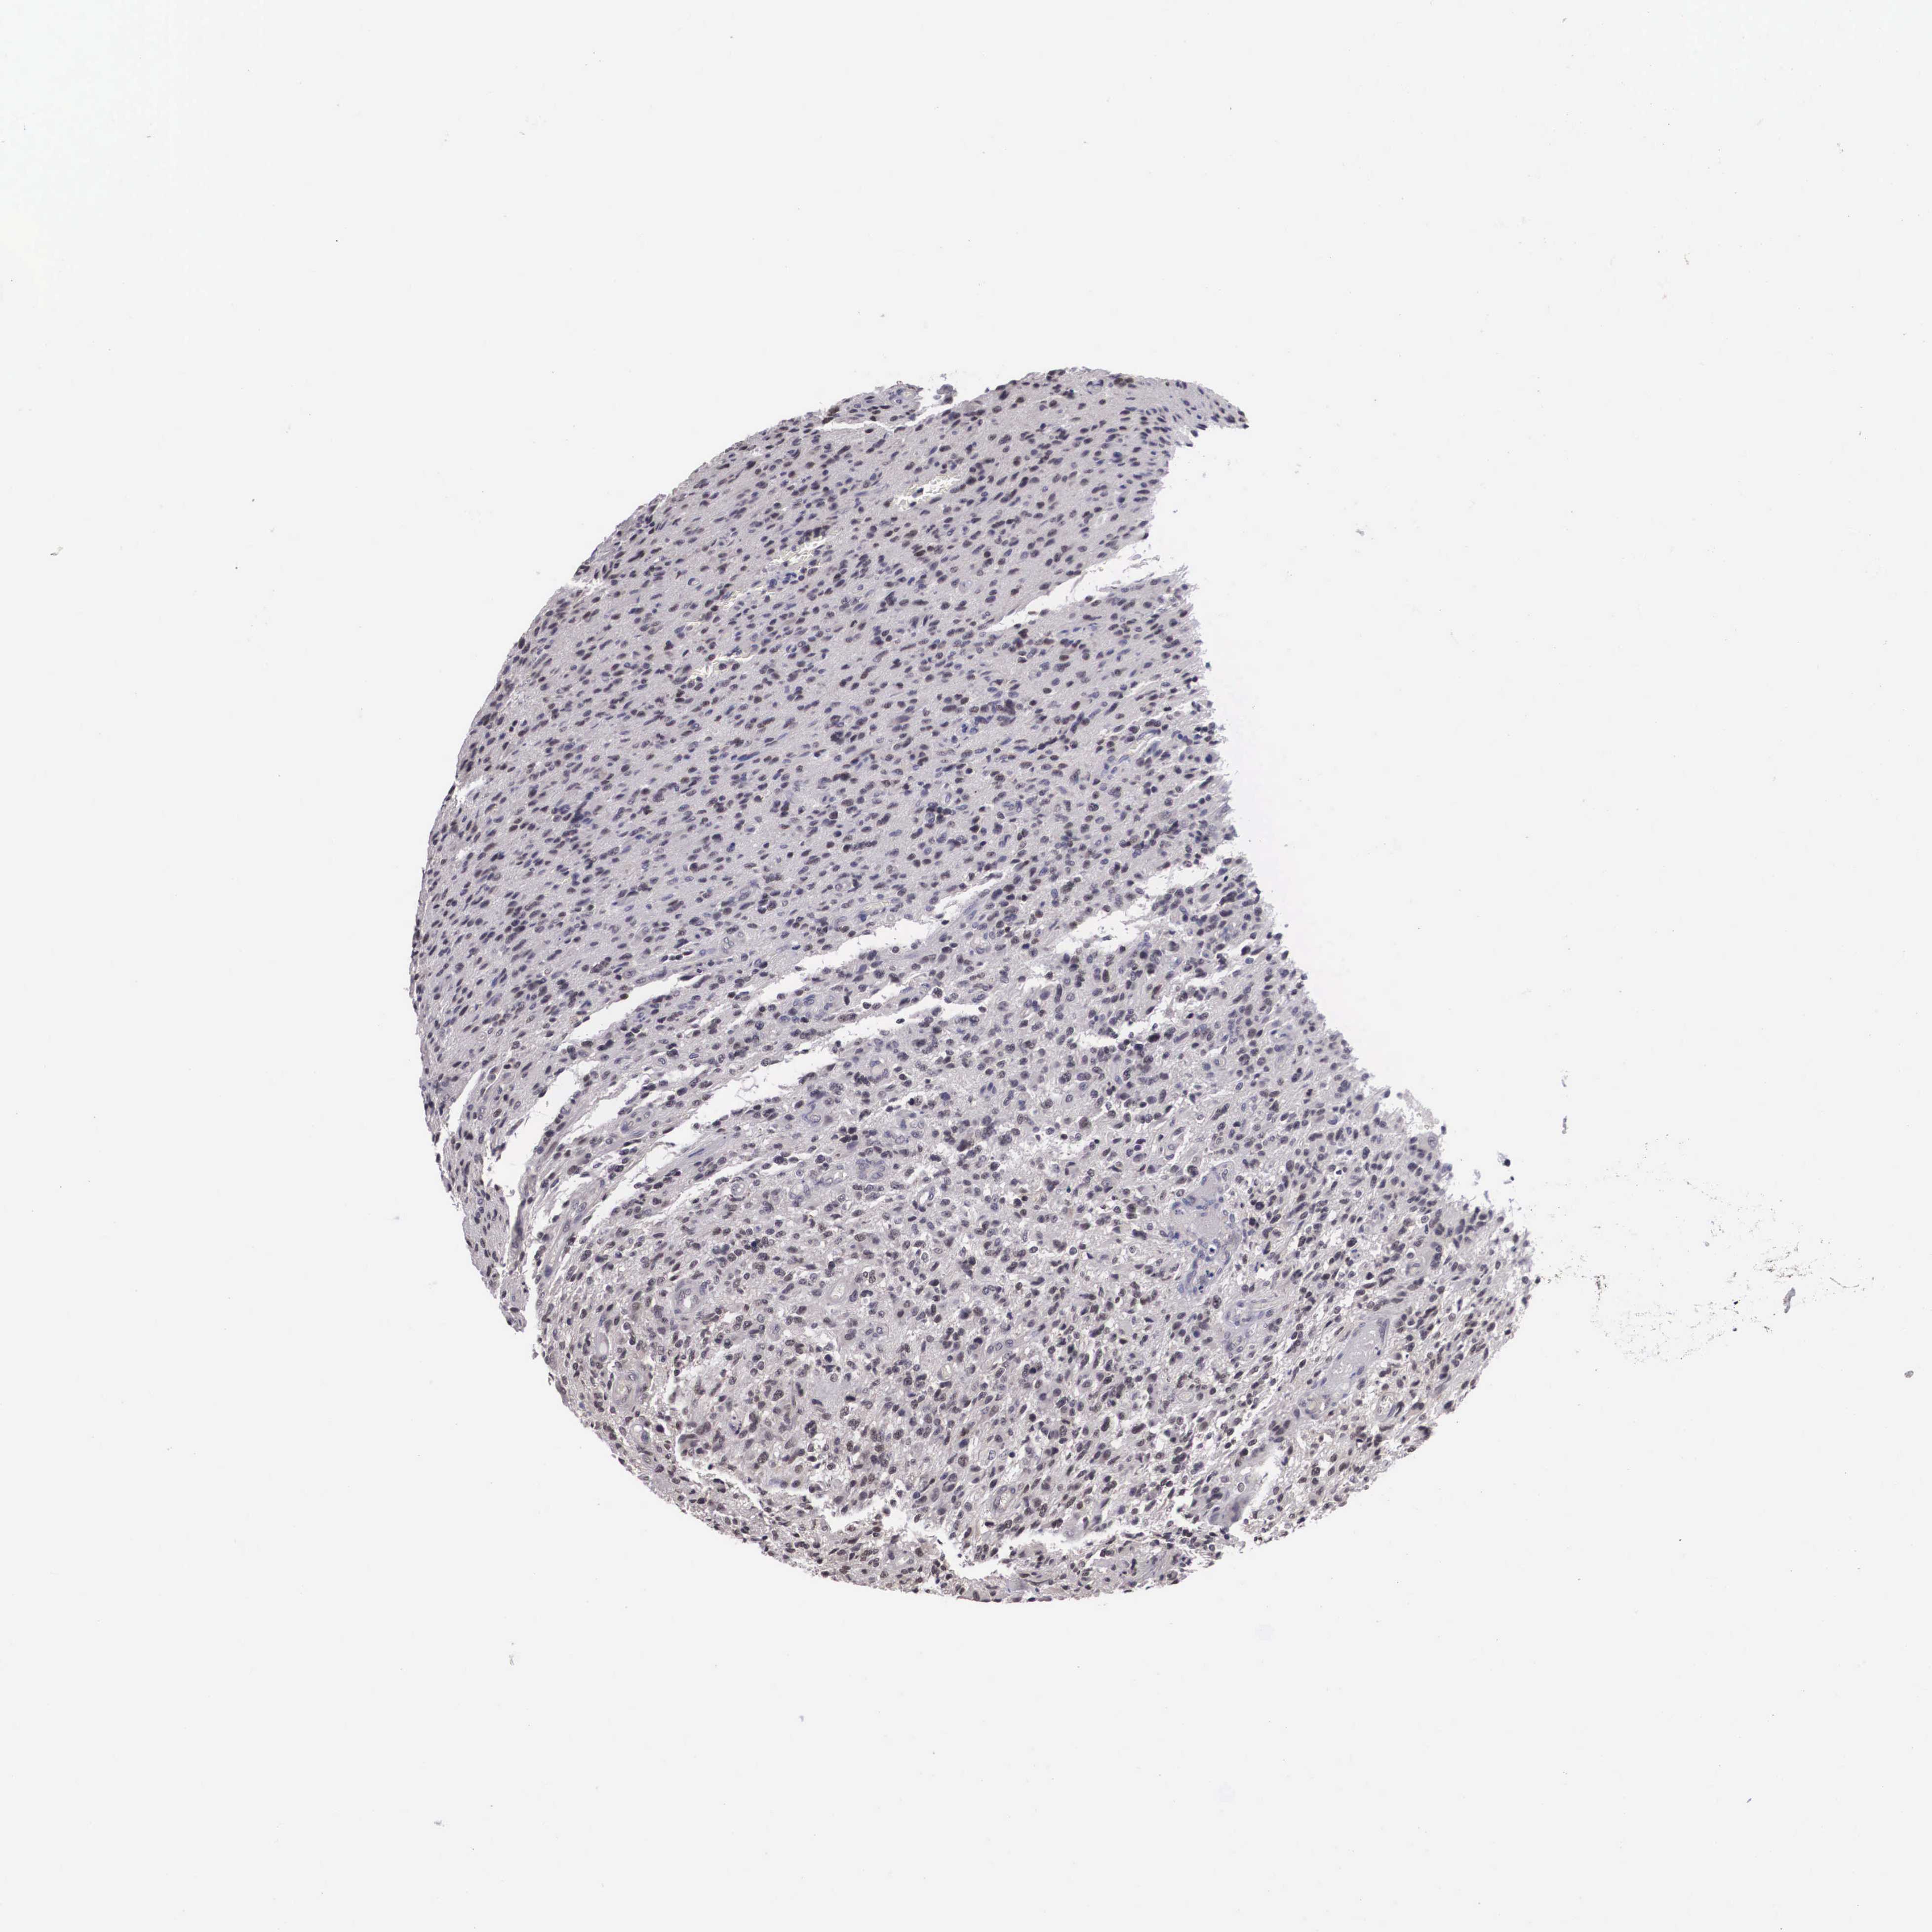

GLIOMA - Protein expressioni

A mouse-over function shows sample information and annotation data. Click on an image to view it in a full screen mode. Samples can be filtered based on level of antibody staining by selecting one or several of the following categories: high, medium, low and not detected. The assay and annotation is described here.

Note that samples used for immunohistochemistry by the Human Protein Atlas do not correspond to samples in the TCGA dataset.

Antibody stainingi

Antibody staining in the annotated cell types in the current human tissue is reported as not detected, low, medium, or high, based on conventional immunohistochemistry profiling in selected tissues. This score is based on the combination of the staining intensity and fraction of stained cells.

Each image is clickable and will lead to virtual microscopy that enables deeper exploration of all samples and also displays staining intensity scores, fraction scores and subcellular localization as well as patient and tissue information for each sample.

Antibody HPA000566

Staining

High

Medium

Low

Not detected

Intensity

Strong

Moderate

Weak

Negative

Quantity

>75%

75%-25%

<25%

None

Location

Nuclear

Cytoplasmic/membranous

Cytoplasmic/membranous,nuclear

Glioma, malignant, High grade

Glioma, malignant, Low grade